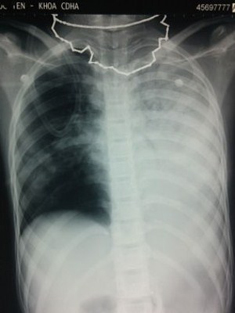

| ẢNh minh họa. |

Khi dị vật bật ra, trẻ sẽ hồng hào trở lại, khóc to và người cấp cứu nên kiểm tra lấy bỏ dị vật đã trôi ra miệng. Cùng với tiến hành cấp cứu bằng thủ thuật trên, nhanh chóng đưa trẻ đến cơ sở y tế gần nhất để được kiểm tra, lấy bỏ dị vật (nếu còn) bằng chiếu chụp Xquang phổi và nội soi khí phế quản.